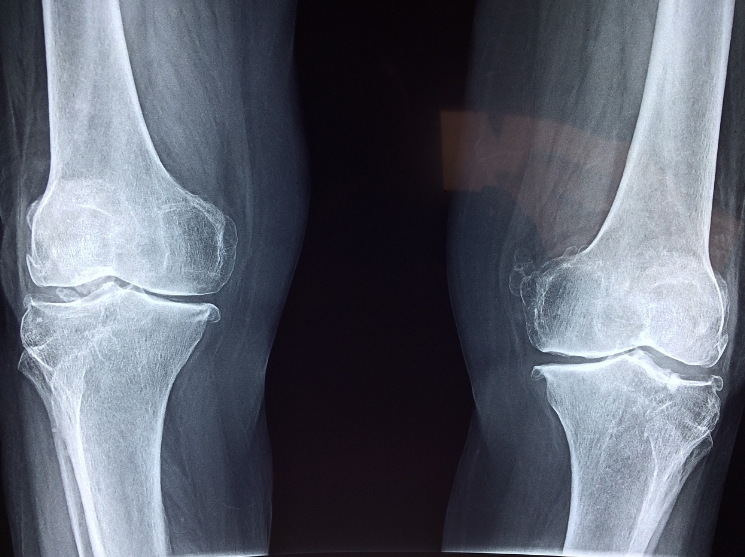

'골다공증'이란 뼈의 밀도와 질량이 감소함으로써, 뼈가 약해지고 쉽게 부러질 위험성이 증가하는 질환입니다.

골다공증은 보통 '침묵의 질병'이라 불리고 있는데, 이는 초기에 뚜렷한 증상이 나타나지 않는 경우가 많기 때문입니다.

가벼운 충격을 받거나 살짝 넘어진 경우에도 뼈가 쉽게 부러질 수 있으며, 특히 손목과 척추, 고관절 부위에서 골절이 자주 발생합니다.

척추뼈가 점차 약해짐으로 인해 압박 골절이 발생하면, 등이 굽거나 키가 줄어드는 현상이 나타납니다.